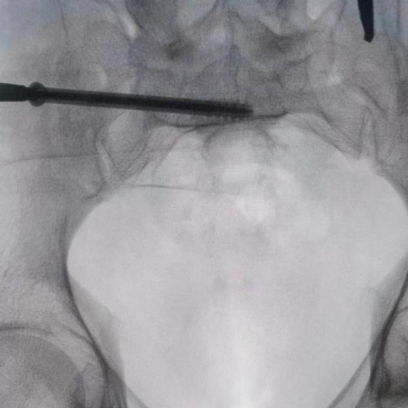

机器人完成患者信息二维图像采集后设计出螺钉置入方向

透视下见置入的骶髂螺钉,位置、长度精准,无丝毫偏差